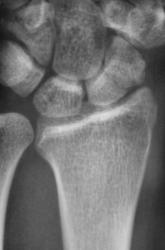

Катенёв Валенти... Дата публикации 15.10.2009, 20:32 Травма неделю тому. Пациент направлен на рентгенологическое исследование лучезапястного сустава с диагнозом "Перелом". Произведено исследование. Ваше мнение коллеги? Чт, 15/10/2009 - 20:36 #1 В.Б. Серов Не на сайте Был на сайте: 3 недели 3 дня назад Зарегистрирован: 16.07.2008 - 10:15 Публикации: 1376 Нужен косой снимок, подтвердить/опровергнуть перелом ладьи. Зри в корень! Чт, 15/10/2009 - 21:37 #2 Наталия Не на сайте Был на сайте: 9 лет 2 недели назад Зарегистрирован: 30.07.2008 - 13:24 Публикации: 538 Перелом ладьевидной кости без смещения виден хорошо. Чт, 15/10/2009 - 21:53 #3 Катенёв Валенти... Не на сайте Был на сайте: 7 лет 5 месяцев назад Зарегистрирован: 22.03.2008 - 22:15 Публикации: 54876 Да. линия перелома в ладьевидной кости, весьма хорошо дифференцируется

Перелом ладьевидной кости без смещения виден хорошо.

Да. линия перелома в ладьевидной кости, весьма хорошо дифференцируется